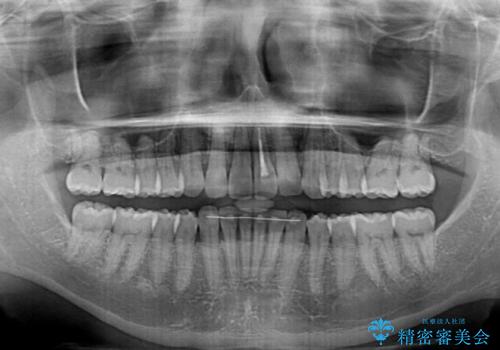

矯正治療後、前歯の形と色が気になるとのことでしたが、大分前に失活している(神経が取り除かれている)歯であり、その影響で変色しているため、オールセラミッククラウンによる補綴治療をおすすめいたしました。